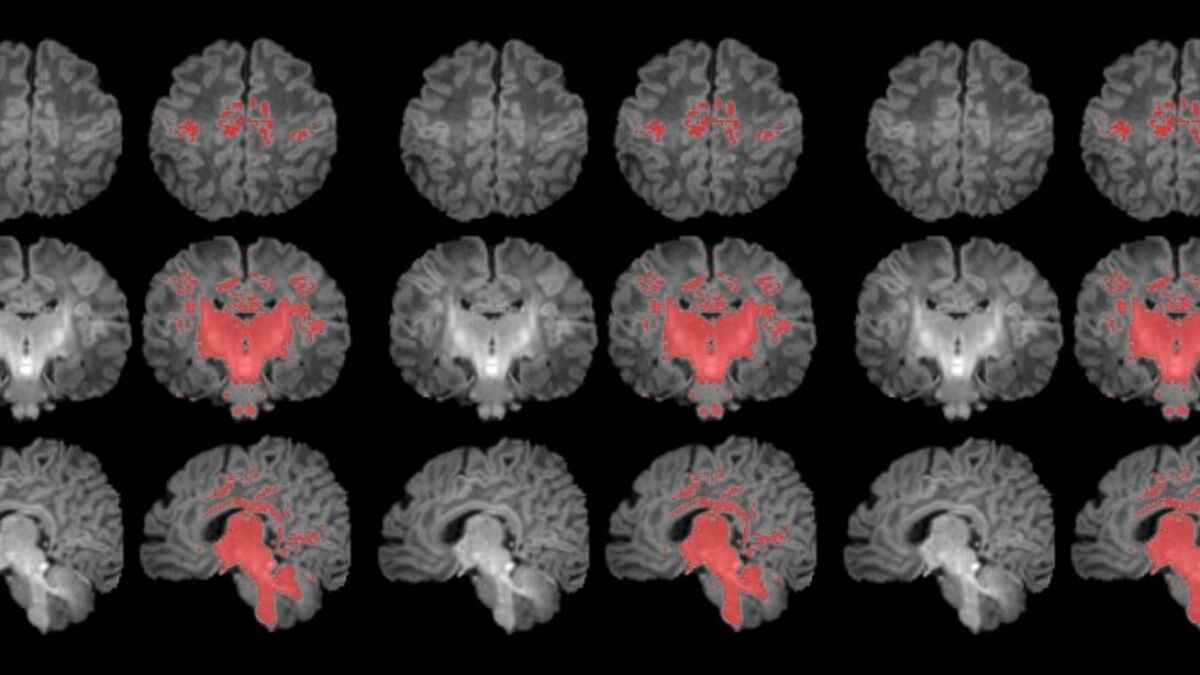

La exposición prenatal a la contaminación del aire se relaciona con una maduración más lenta del cerebro durante el primer mes de vida. Así lo ha revelado el primer estudio que mide con resonancia magnética la mielinización cerebral de los recién nacidos.

La mielinización es un proceso clave en la maduración del cerebro, en que la mielina recubre las conexiones neuronales y las hace eficientes para la transmisión de información. Los recién nacidos de madres expuestas a niveles más altos de partículas finas en suspensión durante el embarazo muestran una mielinización más lenta en esta etapa tan precoz de la vida.

Para llevar a cabo el estudio se reclutó a mujeres embarazadas en seguimiento en el Hospital Clínic Barcelona, el Hospital de Sant Pau y el Hospital Sant Joan de Déu. Se monitorizaron los niveles de contaminantes atmosféricos a los cuales estaban expuestos durante la gestación y, después del parto, se seleccionó a 132 recién nacidos. A estos se les realizó una resonancia magnética antes de cumplir el primer mes de vida para observar el grado de maduración cerebral según sus niveles de mielinización.

Los resultados muestran una correlación clara entre una mayor exposición materna a PM2.5 durante el embarazo y una menor mielinización en el cerebro de los recién nacidos.